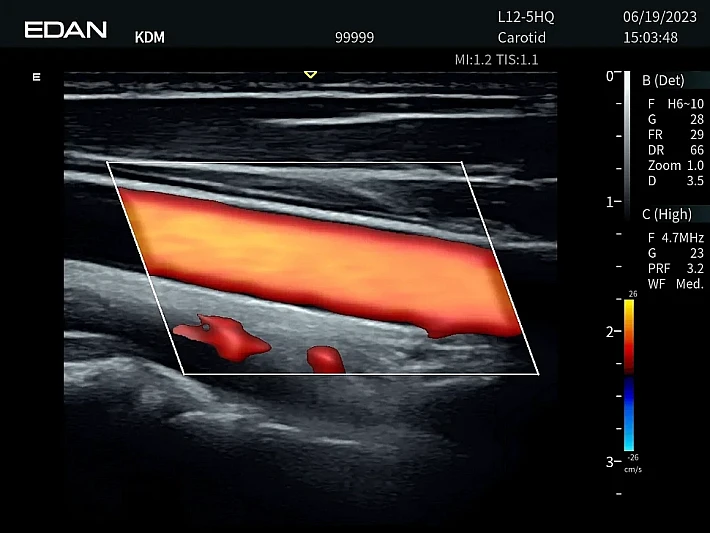

Медицинское оборудование и сервисное обслуживание